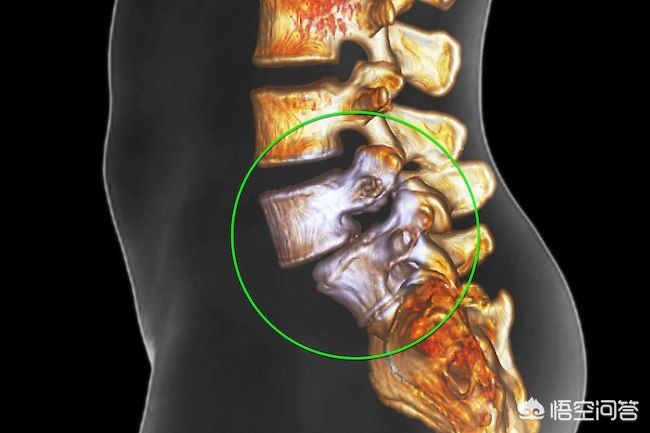

第二,脊柱滑脱的患者不建议做小燕飞。存在脊柱滑脱的患者,本身由于其脊柱的不稳定,椎体与椎体之间已经发生了滑动,那么此时再进行过度的挤压训练,很有可能导致滑脱的加重。大家看下图就会明白,为什么脊柱滑脱的患者是不适合做燕飞的。椎体与椎体之间已经发生了滑动,那么在做不正确的动作,可能会导致滑坡的加重。